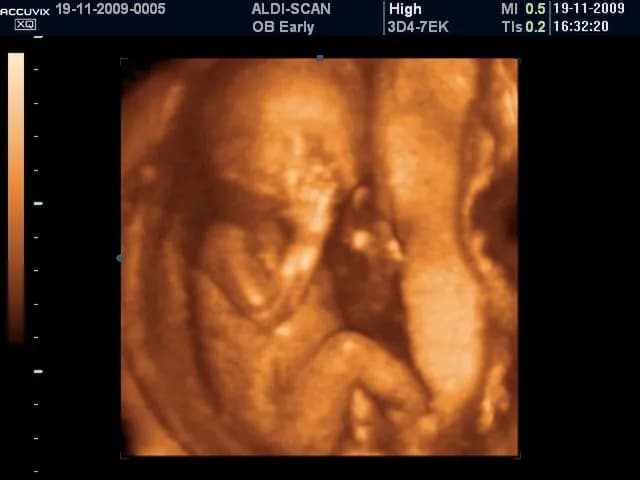

Rozwarcie na 2 palce: ile cm to jest i co oznacza w porodzie?